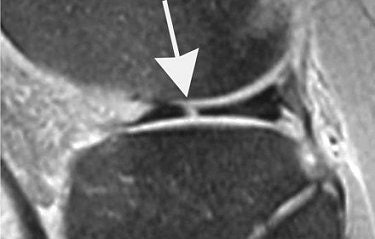

![]() |

| Marching cleft sign in discoid lateral meniscus indicates radial meniscal tear in 21-year-old man. Conventional sagittal proton density images (2,000/20) with fat saturation show vertical high signal (arrows) extending through adjacent two body segments, indicating cleft marching centrally and anteriorly indicating radial tear. |